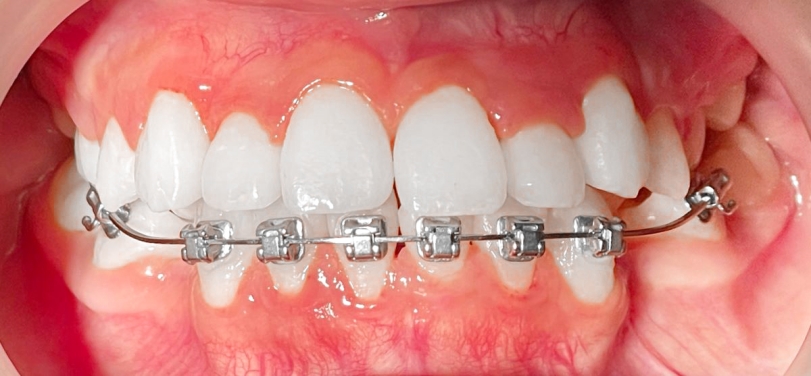

正在換牙期的小茹因齒列先天發育異常,從小就咬合不良,雖然能正常飲食,也不影響說話,但是一口亂牙令她相當困擾,因此在11歲時被媽媽帶來台北慈濟醫院齒顎矯正科評估。全口X光中看到小茹的牙齒不但亂,還有先天缺牙與阻生齒。陳宜宏醫師建議早期進行齒列矯正,也就上述狀況分別處理治療,迄今矯正一年半,先拆除上排矯正器,小茹的齒列與外觀已大幅改善,平整的門牙讓她更有自信,下排牙齒目前持續矯治中。

以小茹為例,經診斷其有:上顎牙弓發育不足、輕微戽斗與門牙排列紊亂、上排雙側犬齒阻生與第二小臼齒先天缺牙、下排雙側第二大臼齒阻生與右下第二小臼齒萌發方向異常。由於狀況複雜,陳宜宏醫師建議以固定矯正器加上顎兩支骨釘為主要治療方式,先針對長不出來的兩顆犬齒做電燒,讓埋在牙齦裡的齒面露出,黏上矯正器;接著拔掉兩顆上顎第二乳臼齒與打上骨釘,利用其將第一小臼齒與犬齒向後拉,同時上門齒慢慢排列整齊,考量小茹上顎先天缺牙且上下牙齒顆數必須對稱,故拔除下顎兩顆第一小臼齒來獲得空間,並將下門牙排列整齊。